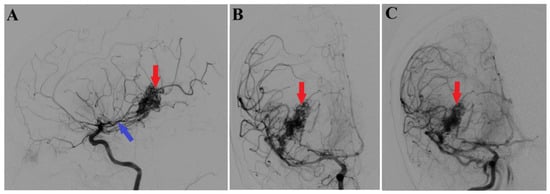

A 44-year-old patient was admitted to our clinic for sudden left hemiparesis MRC 1/5 occurring in the apparent health status 48 h prior to admission, followed by the deterioration of consciousness that become gradually worse, with the patient becoming comatose. She was admitted to our clinic with GCS = 7 points (eye response—2 points, verbal response—2 points, motor response—3 points), orotracheally intubated, and mechanically ventilated. Neurological examination on admission revealed a left hemiparesis, predominantly in the brachial region and comatose state. A brain non-contrast CT scan revealed a voluminous right fronto-temporal intraparenchymal hematoma with panventricular infiltration, significant mass effect on the right lateral ventricle, and 1.5 cm displacement of the midline. Otherwise, normal cerebroventricular CT appearance was seen (Figure 1). Angiography was performed through the selective injection of the internal carotid artery bilaterally, right external carotid artery, and left vertebral artery. Right temporal arteriovenous malformation with arterial afferents from the right anterior choroidal artery and right-sided middle cerebral artery was observed, Spetzler Martin grade III (Figure 2). A nidus of approximately 2/1 cm in size with several intranidal aneurysms was also observed (Figure 3). A single vein was draining into the right cavernous sinus, through an intermediate venous source.

Figure 2.

Preoperative 2D digital subtraction angiography. Profile (A) and frontal (B) 2D DSA highlights the right temporal arteriovenous malformation (red arrows), found as well in 2D DSA reconstruction (C). Moreover, profile 2D DSA (A) shows a slight dilatation of the anterior choroidal artery (blue arrow).

Figure 3.

Preoperative 3D DSA rotational angiography. The 3D reconstruction of rotational DSA (A) depicts the tridimensional topography of the arteriovenous malformation (red arrows). In high-resolution image (B), multiple intranidal sacullar and fusiform aneurysms were found (blue arrows).